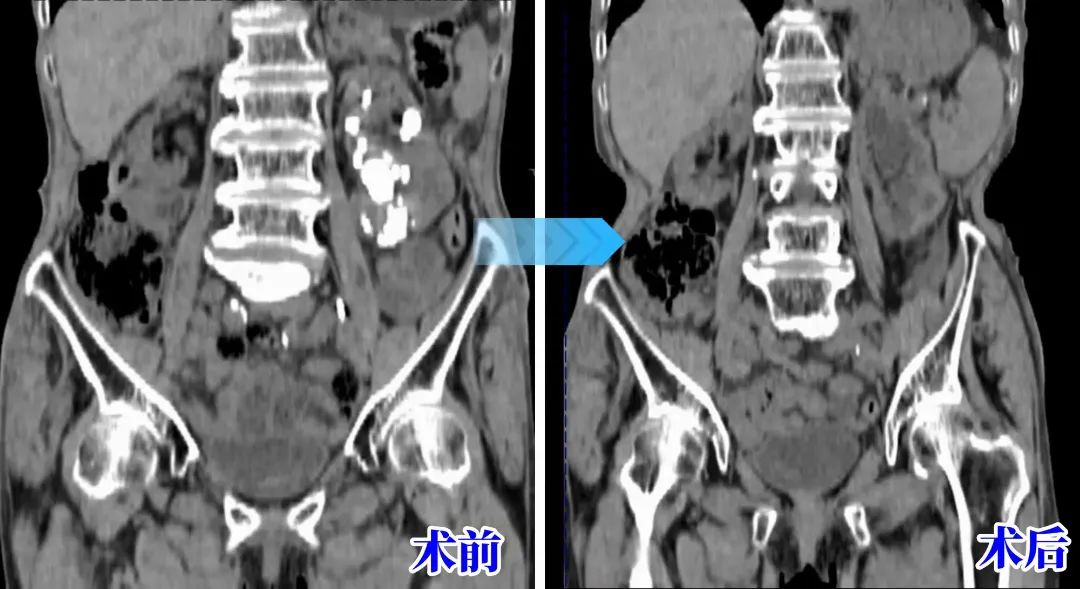

影像学检查

术后患者恢复良好,14日后顺利出院,影像学提示患者左肾结石完全清除,腹痛及发热情况再也没有出现。自此,困扰患者20余年的结石问题终于得到解决。